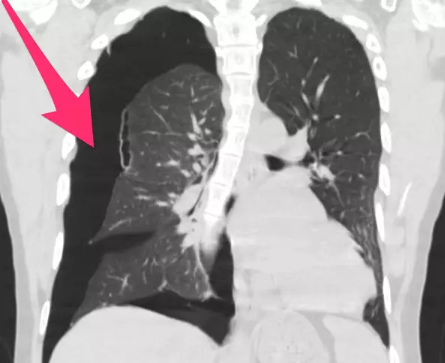

Chance Ammirata, 18, a regular vape smoker shared images of his lungs on Twitter and stated that the collapse of his lungs and black dots visible in it are results of excessive vaping.

He released a scanned image of his lung and showcased that the there is a vent through which the air leaks between chest wall and lung that eventually let the blisters inside the lung.